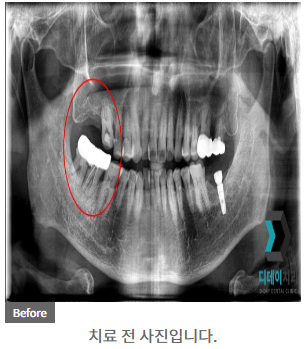

230302

230327

임플란트의 성공 여부는 나이보다는 전신 건강 상태와 구강 상태에 더 큰 영향을 받습니다.

물론 나이가 들수록 뼈의 밀도가 낮아지고 회복 능력이 떨어지는 것은 사실이지만, 이는 개인차가 크고 적절한 처치로 극복할 수 있습니다.

예를 들어, 뼈 밀도가 낮은 경우 뼈 이식술을 병행하여 임플란트의 성공률을 높일 수 있습니다.

| 본 게시물은 의료광고법 제56조 1항을 준수하여, 의료 정보 제공 및 병원 홍보를 목적으로 디데이치과의원에서 직접 작성하였습니다.다만, 블로그에서 제공해 드리는 정보는 참조용으로만 활용하시고, 정확한 개인의 증상 파악은 의료기관에 직접 내방하시어 의료진을 통해 확인하실 것을 권유 드립니다.치과에서 진행되는 모든 시술 및 수술(임플란트 포함)은 개인에 따라 부작용 (염증, 출혈, 부기, 신경 손상 등) 가능성이 있습니다. 따라서 사전에 의료진과 충분한 상담을 통해 결정하시길 바랍니다.게시물의 치료 사진은 실제 본원에서 모든 치료 과정을 마친 환자분의 동의하에 촬영되었습니다. 전후 사진은 동일인이며, 동일 조건하에 촬영되었음을 밝힙니다. |